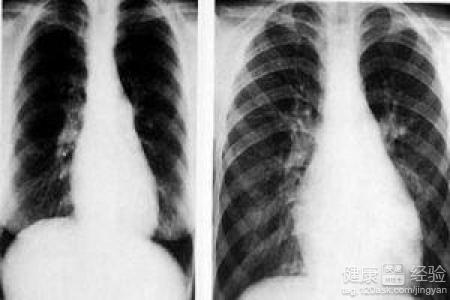

1肺源性心髒病是一種非常嚴重的疾病,都是因為之前肺部疾病沒有控制住造成的,所以我們如果出現肺部不適的時候應該早點去醫院治療。